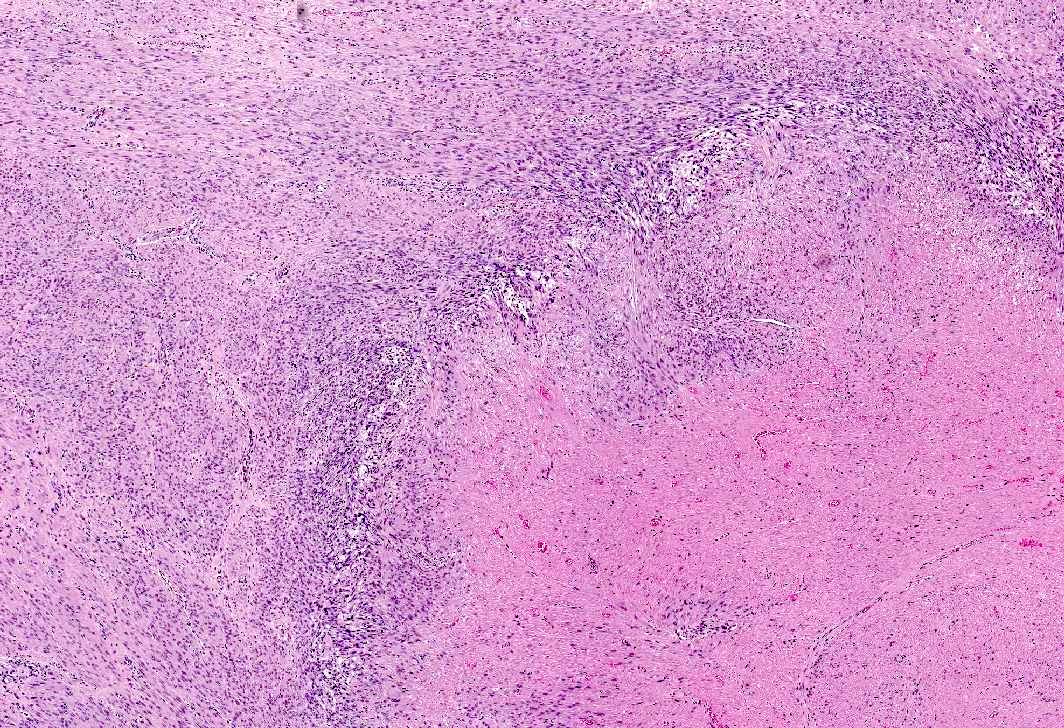

- Leuprolide (Lupron) related changes in leiomyomas

- Central geographic areas of edema and hydropic degeneration

- Subsequent hyaline degeneration

- Necrosis with surrounding hypercellularity (may vary from infarct type, coagulative or uncertain type)

- Lymphoid aggregates

- Comment: The leiomyomas exhibit degenerative changes including large areas of edema, hydropic to hyaline degeneration and necrosis associated with lymphoid aggregates. Most foci of necrosis appear infarct type, although some foci are difficult to differentiate from coagulative necrosis and would be best classified as uncertain type; however, given the recent history of Lupron therapy, these changes are most likely attributed to such therapy.